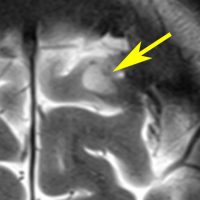

病理はとれないので確定できませんが,おそらく微小過誤腫 microhamartomaなのでしょう